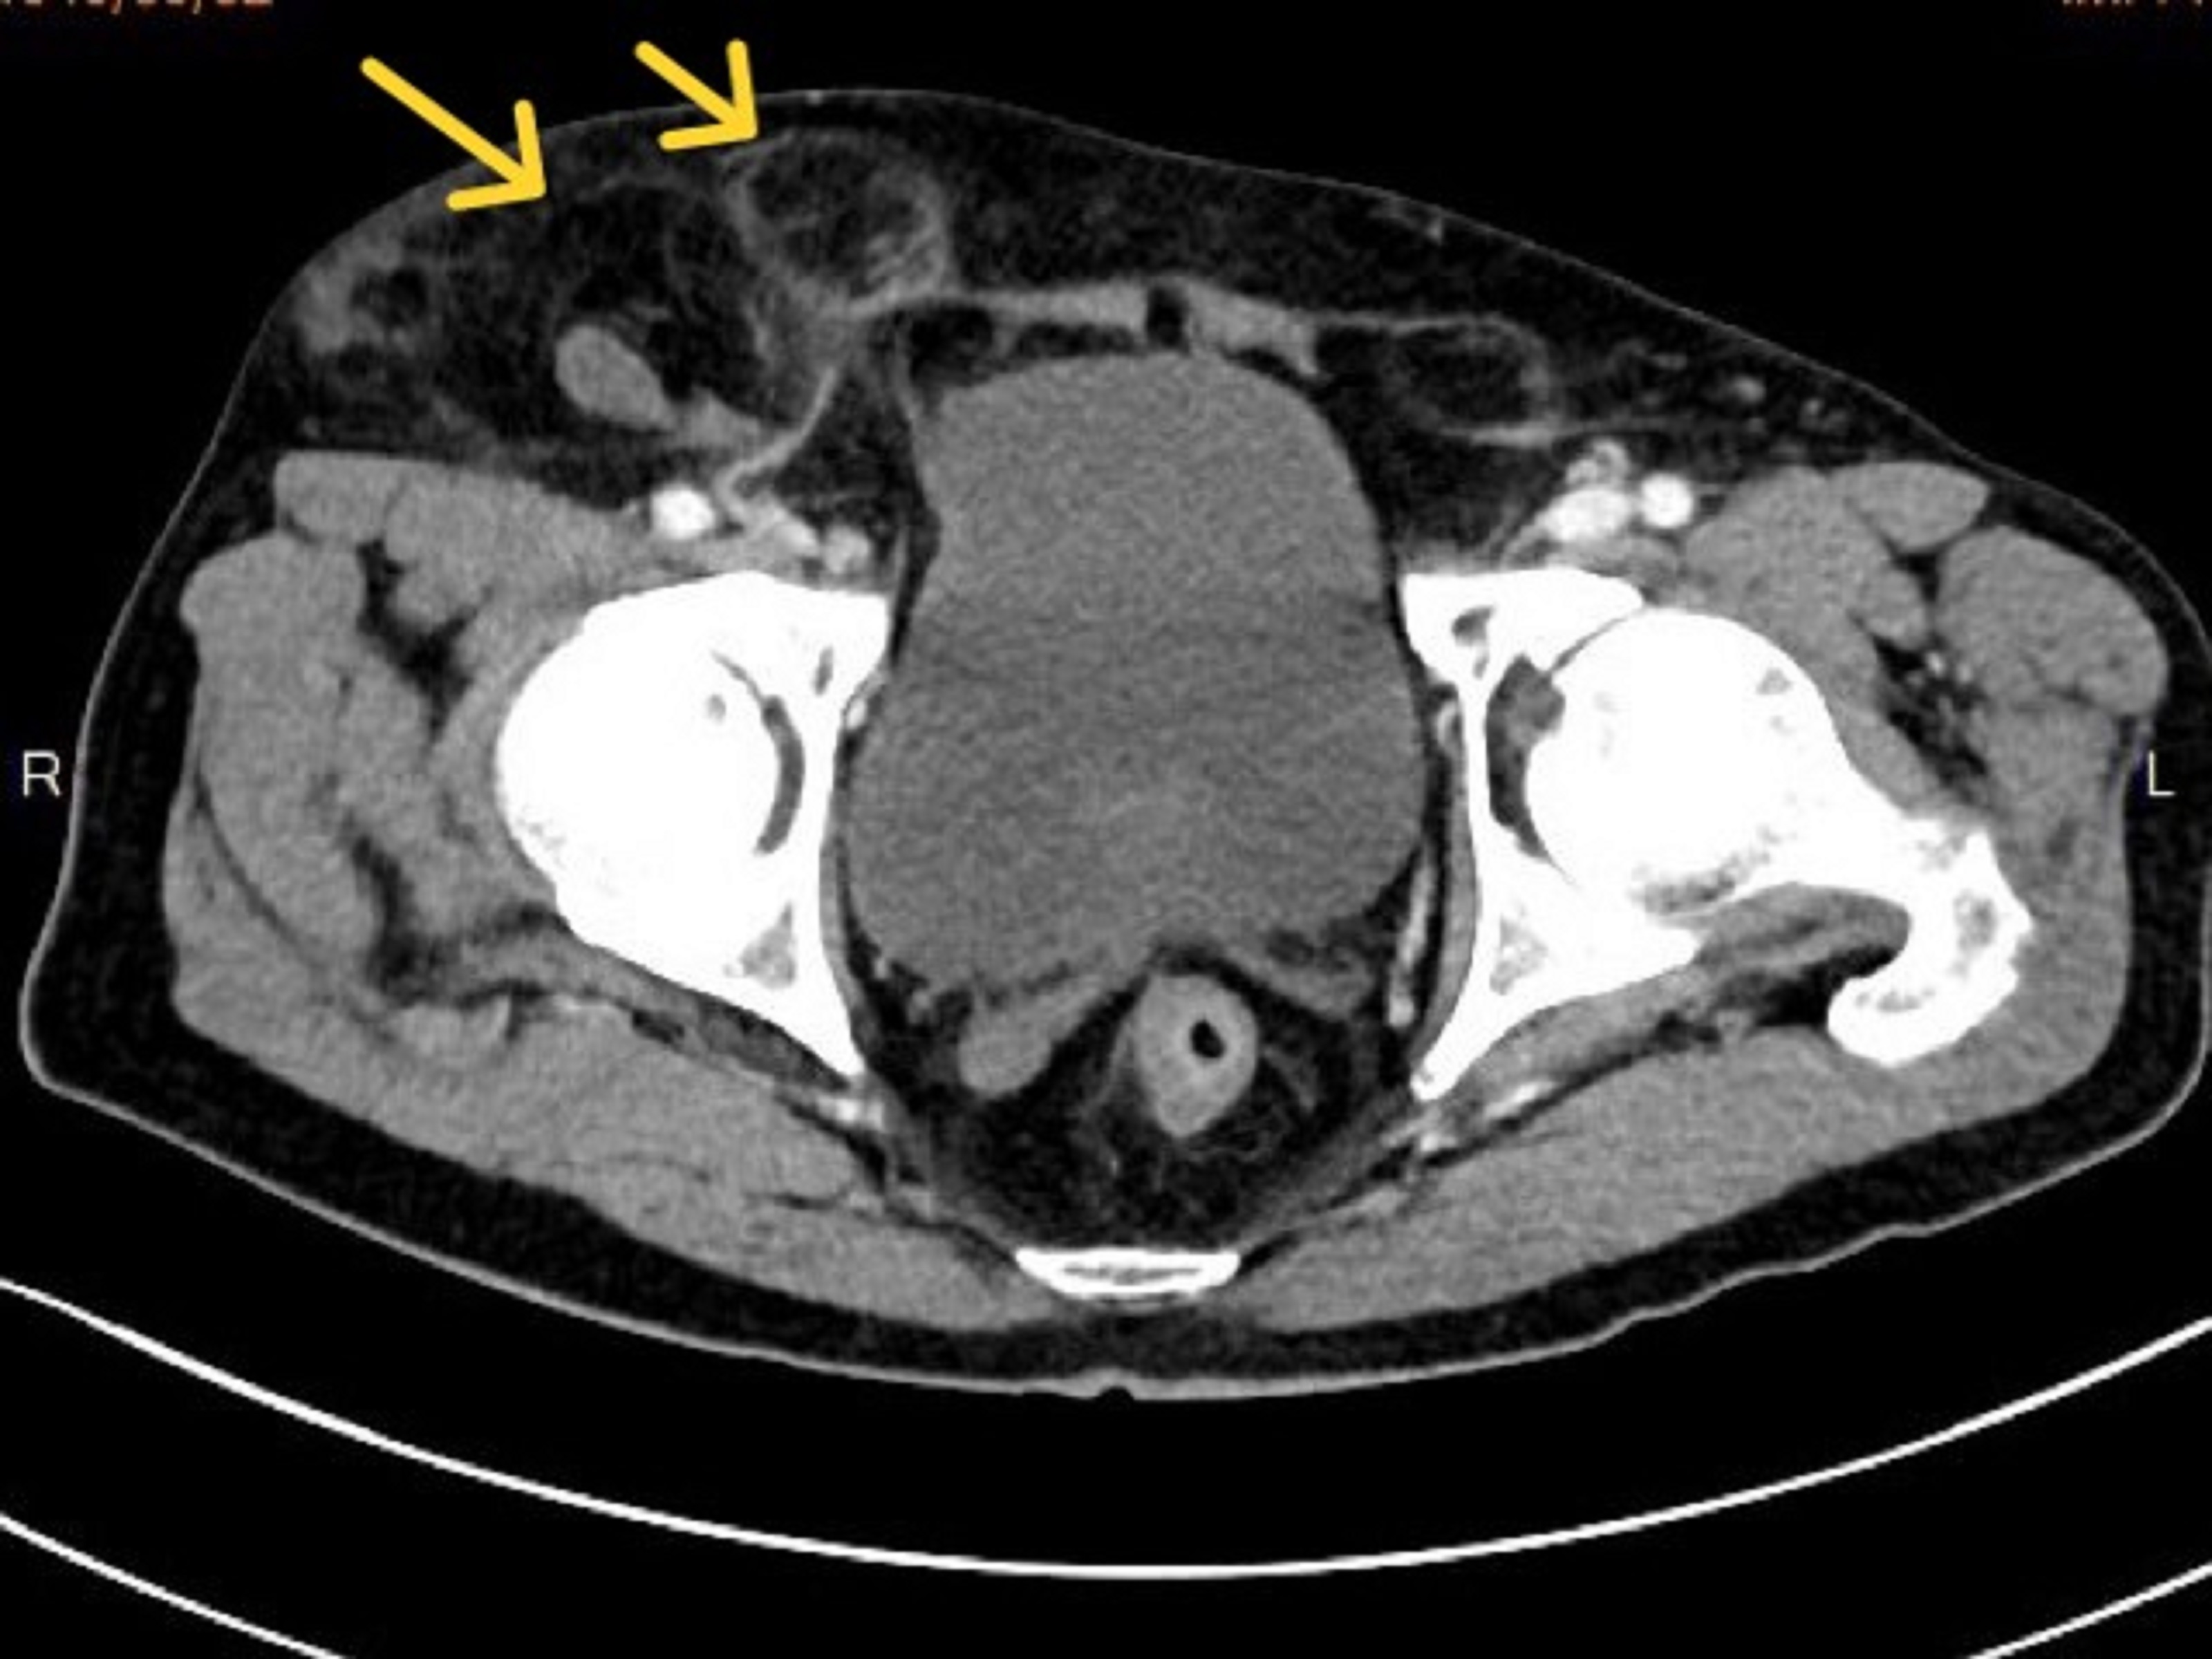

年近八旬的陳伯伯,年輕時因腹股溝疝氣開過兩次傳統手術,近年來經常復發,右下腹靠鼠蹊部位時常「鼓一包」,日前突腹痛難耐就醫,醫師原想徒手幫他復位,但因疝氣造成的突起物實在過於巨大(20*15*10公分),難以一手掌握,影像檢查更發現是罕見的「雙疝氣」,部分小腸及大量網膜組織嵌頓,形成兩個大小不一的疝氣囊,需立即手術以避免腸道壞死。

蘇文隆說,手術過程中,確認病人同時發生股疝氣(femoral hernia)及間接型腹股溝疝氣(inguinal hernia),除將嵌頓的小腸及網膜復位,並使用立體剪裁人工網膜修補疝氣孔,以腹腔鏡縫合腹膜,及切除一小段已壞死的嵌頓小腸,手術歷時七小時終於順利完成。陳伯伯康復出院後回診,疝氣囊已完全消失,右側腹股溝回復平整,總算擺脫「頂著一大包走路的困擾與不適